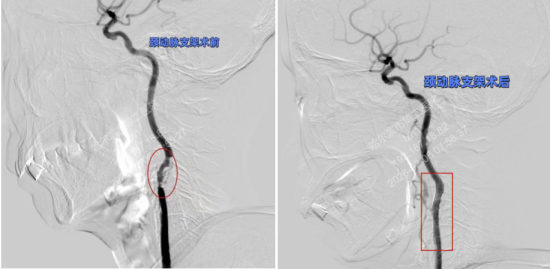

检查结果证实了专家的预判,冠脉CT显示,患者左冠状动脉和右冠脉存在严重的重度狭窄,这意味着李女士不仅面临脑卒中风险,更随时可能突发急性心肌梗死的危险。病情就是命令,神经内科专家迅速启动泛血管疾病管理中心多学科会诊(MDT)机制,心内科专家紧急介入。面对心、脑两处极高危病变,医生们犯了难。经过MDT团队深入评估,一致认为:冠状动脉病变是当前对生命最直接、最迫切的威胁。团队果断决策,“先心脏,后颈动脉”,优先为李女士实施冠状动脉支架植入术,稳住了生命中枢。

然而,新的挑战接踵而至。因李女士体重较轻,肌酐略有增高,若同时接受两次需要使用造影剂的大型介入手术,将面临较高的肾损伤风险。一切以患者安全为中心,团队再次展现了精细化、个体化管理的水平。他们没有追求速度,而是科学地将颈动脉支架手术安排在心脏手术两天后进行,给予身体充分的代谢恢复时间。两天后,第二颗“炸弹”也被成功拆除。手术过程平稳,患者未出现任何并发症。